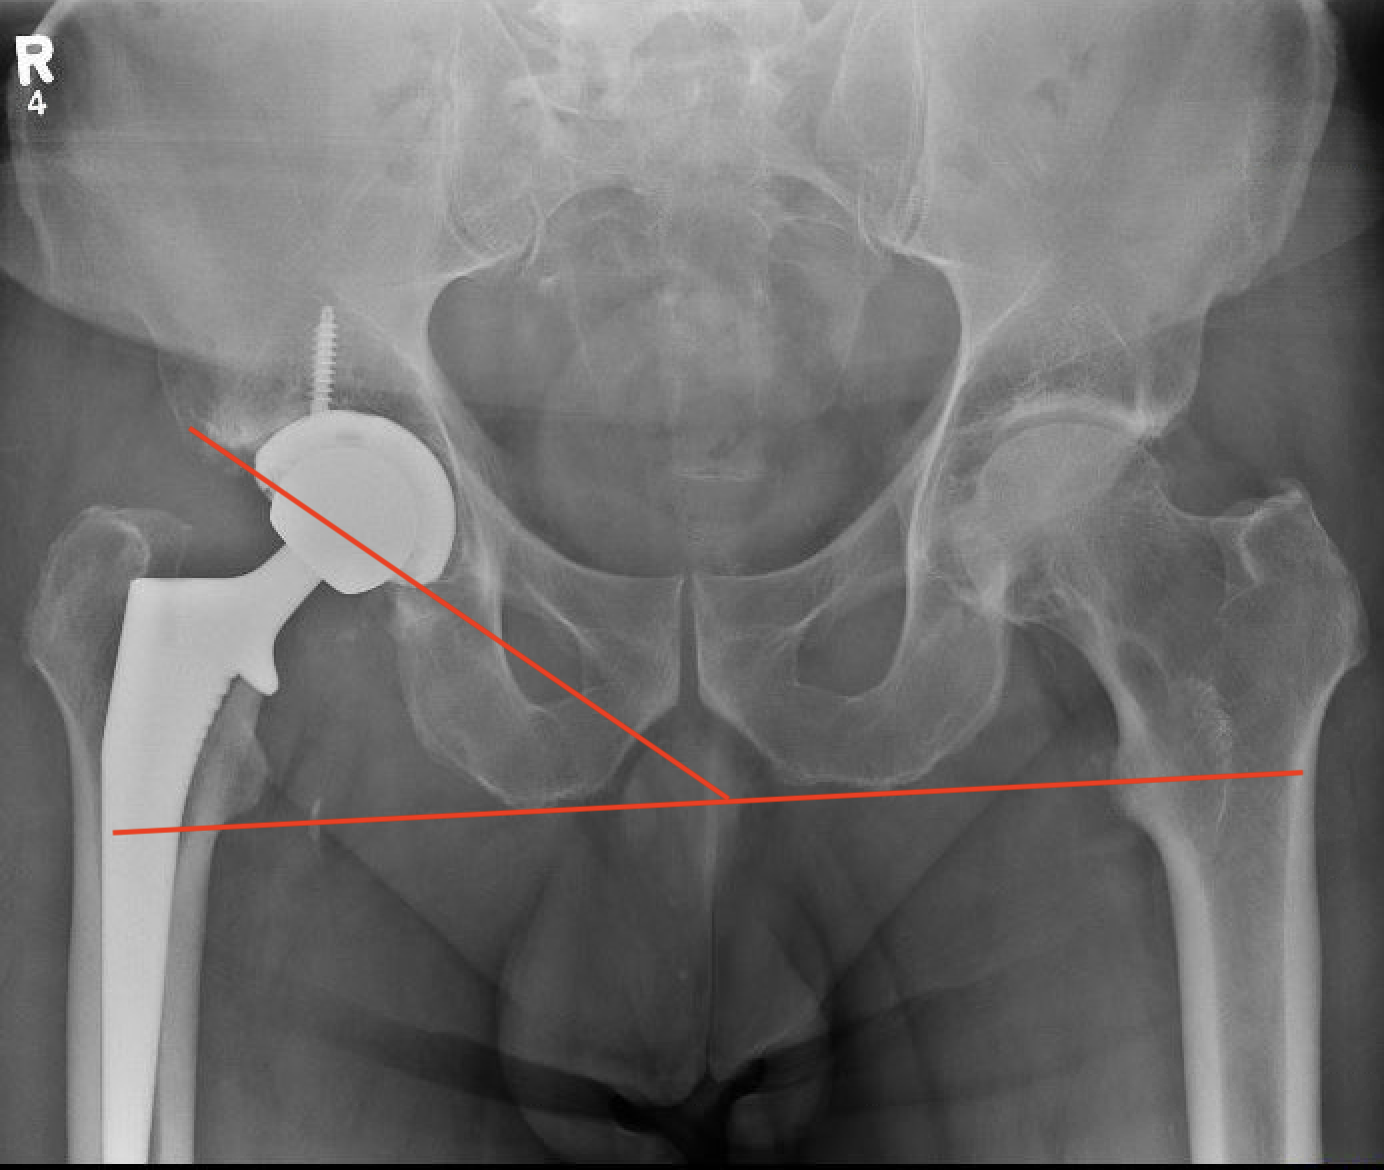

Minimize leg length discrepancy

Measuring acetabular position

Cup inclination

Cup anteversion